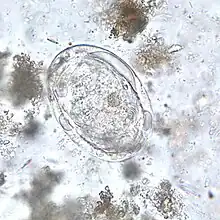

[[Imagem: ![]() Ovo de S. japonicum | |||||||||||||||||